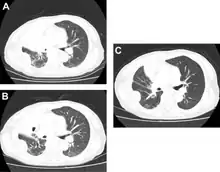

Docetaxel for non-small-cell lung cancer a) before b) tumor response after two cycles c) after 4 cycles